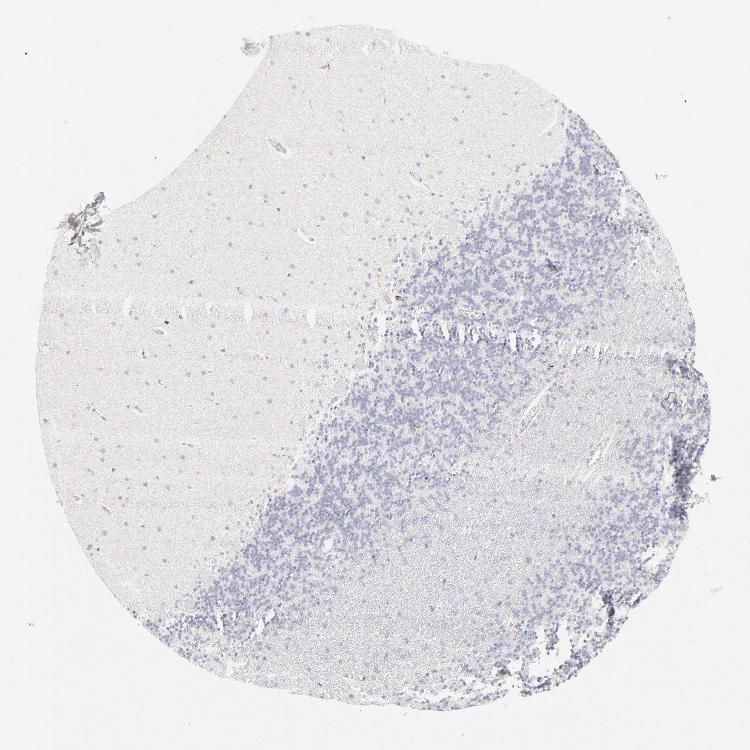

BRAIN CEREBELLUM Show tissue menu

CEREBELLUM - Expression summary

CEREBELLUM - Antibody stainingi

Antibody staining in the annotated cell types in the current human tissue is reported as not detected, low, medium, or high, based on conventional immunohistochemistry profiling in selected tissues. This score is based on the combination of the staining intensity and fraction of stained cells.

Each image is clickable and will lead to virtual microscopy that enables deeper exploration of all samples and also displays staining intensity scores, fraction scores and subcellular localization as well as patient and tissue information for each sample.

Antibody HPA003316Antibody HPA003479

Purkinje cells Not detectedNot detected

Cells in granular layer Not detectedNot detected

Cells in molecular layer Not detectedNot detected